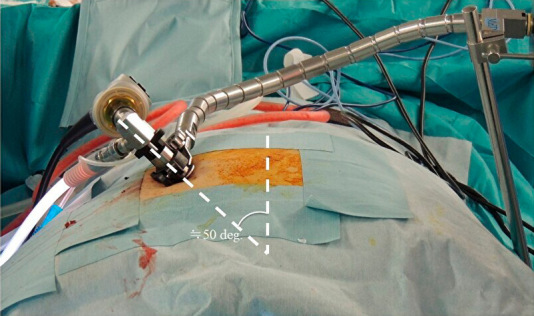

Technical note: The patient was operated in a prone position under general anesthesia. At a preoperatively determined distance from the midline, an 18-mm-long longitudinal incision was conducted, and using a 25-degree microendoscope, the operation was carried out. The endoscope was placed at an inward angle of approximately 50 degrees in the vertical direction. The ribs adjacent to the disc were identified, and the disc was exposed by resecting the ribs using a surgical high-speed drill while preserving the cortical bone of the ribs on the pleural side. The herniation was identified by drilling the ventral side of the disc and was then successfully removed. After discectomy, the dura mater expanded ventrally. Three male patients (mean age, 47.3 years) were treated, with 20 weeks of follow-up on average, 237.7-min mean operative time, and 26.7-mL mean blood loss. The average preoperative modified Japanese Orthopedic Association score was 5.2/11, which improved to 9.5/11 postoperatively, with a 75.6% average recovery rate. The 10-s step test score improved from an average of eight times preoperatively to 20 times postoperatively. No serious perioperative or postoperative complications or residual rib pain were observed.

Conclusions: The proposed TCMED approach for treating central TDH that causes myelopathy allows for safe access to the level of the posterior vertebral wall using the rib as a landmark for resecting the rib head without opening the chest. Using the angled microendoscope and curved surgical instruments, the central TDH, located ventral to the spinal canal, can then be safely and effectively resected without spinal cord retraction.